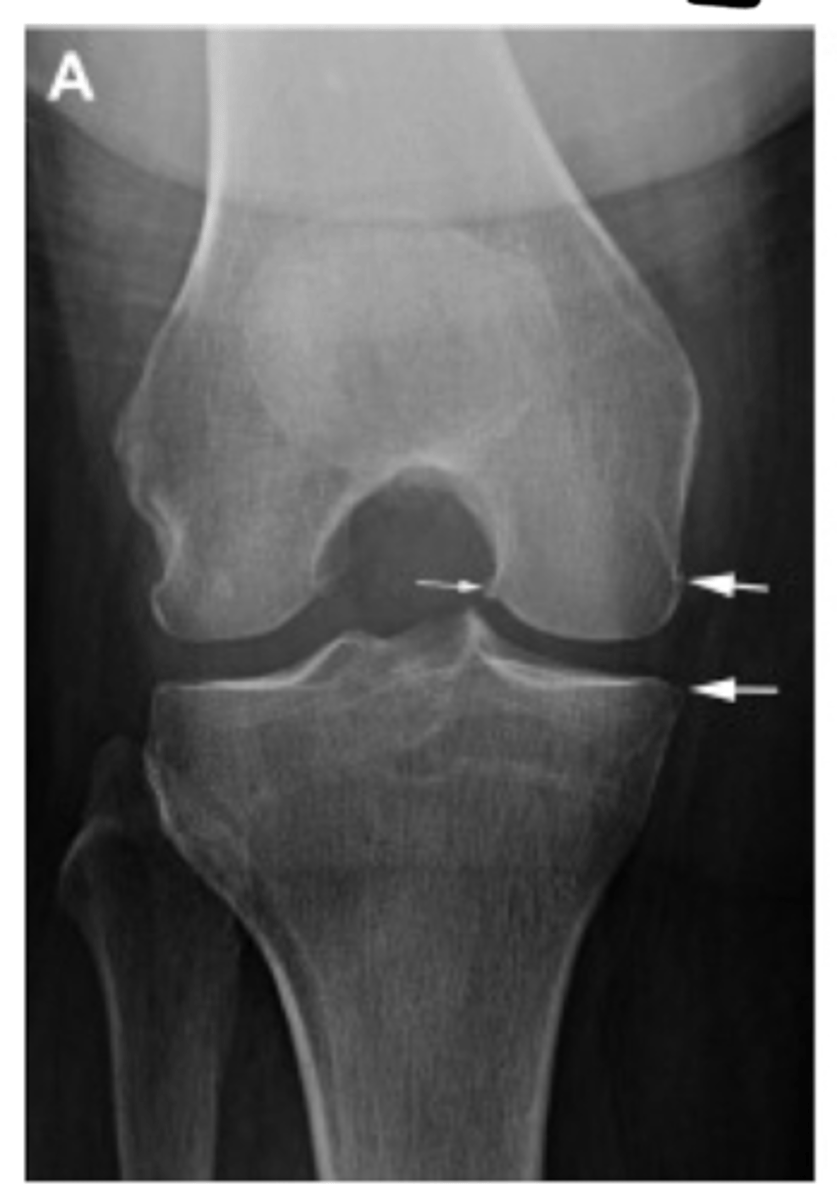

Grade I = minimal osteophytes w/ no problems w/ space or cartilage

Define the Kelgren Lawrence grade. How do you know?

Grade II = 1 definite osteophyte w/ NO space narrowing

Grade III = marginal osteophytes w/ space narrowing + sclerosis & multiple osteophytes

Grade IV = obliteration of joint space (bone on bone)